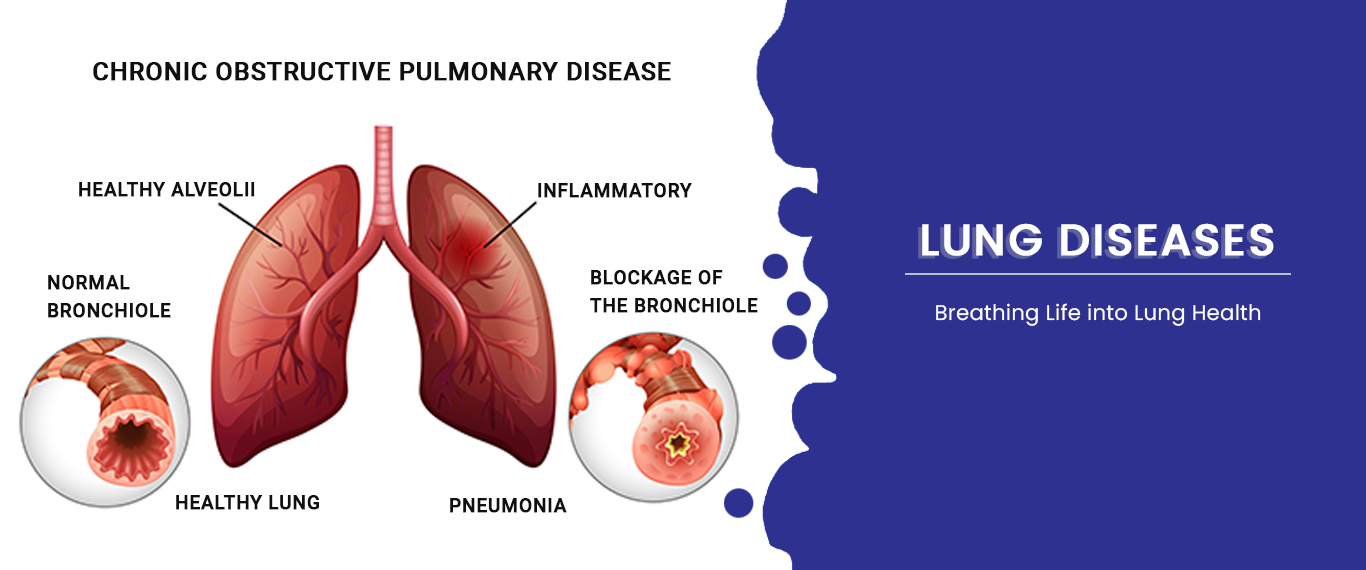

COPD

Chronic Obstructive Pulmonary Disease (COPD) is a progressive lung condition causing airflow obstruction, breathing difficulty, and coughing.